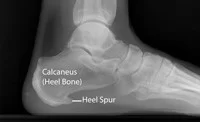

Άκανθα πτέρνας

Αν και σε πολλούς ασθενείς που έχουν πελματιαία απονευρωσίτιδα συνυπάρχει και άκανθα πτέρνας, η ύπαρξη της δεν συμβάλλει στην δημιουργία της νόσου. Μόνο το 5% των ανθρώπων που έχουν άκανθα πτέρνας αναπτύσσουν πελματιαία απονευρωσίτιδα

Οι ακτινογραφίες μπορεί να βοηθήσουν προκειμένου να αποκλειστούν άλλες αιτίες πόνου. Σε εμμένουσες καταστάσεις που δεν υποχωρούν με την συνηθισμένη αγωγή μπορεί να γίνει μαγνητική τομογραφία